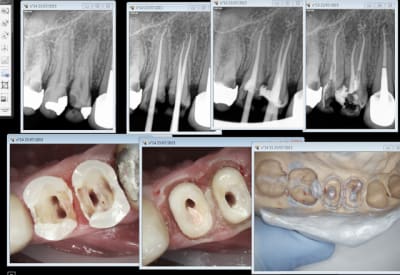

Non, en 2 séances. 1 endo empreinte et 2 pose ic coiffe.

Sur dent de lait c'est pulpo ou extrac.

chicot je réitère: où est l'intérêt de garder des dents dans un tel état chez un enfant de 9 ans laisse une chance à dame nature de mettre la sept à la place. Enfin, ce n'est que mon avis!!!!!!

Patience, les spé en MBD vont bientôt sortir et on peut espérer qu'un peu à la fois des services hospitaliers privés ou publics plus nombreux s'intéresseront à l'affaire. A noter que le principal obstacle pour le public était la Ngap, maintenant c'est bon. Clairement ce genre de cas est à régler en 1 fois sous AG en essayant idéalement de garder les 2d molaires lactéales (pour tenir les 6 ans) et les canines (histoire de préserver une occlusion), les reconstitutions sur incisives lactéales ne tiennent pas et les 1ere molaires lactéales ne "servent à rien" donc si cariées on enlève.

Pour les 6 ans effectivement vu le contexte si bio à faire, çà se transforme souvent en extraction.